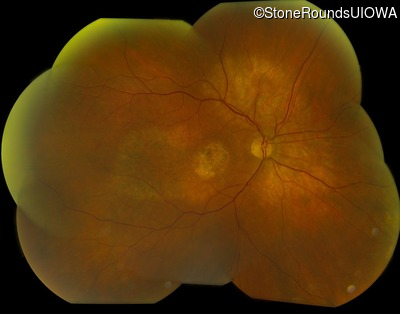

Fundus Montage - Left - 20/125 +1

Exemplar